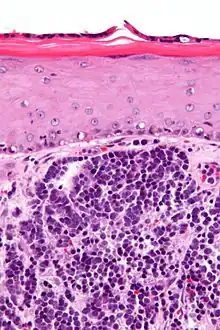

| Micrograph of a Merkel cell carcinoma. H&E stain. | |

Diagnosis of MCC begins with a clinical examination of the skin and lymph nodes to determine suspicious areas for further investigation.[28] Definitive diagnosis requires examination of biopsy tissue to identify its histopathologic features.[6][28] An ideal biopsy specimen is either a punch biopsy or a full-thickness incisional biopsy of the skin including full-thickness dermis and subcutaneous fat. On light microscopy, MCC shows basaloid tumor nests with neuroendocrine features ("salt and pepper" chromatin, scarce cytoplasm, and brisk mitotic activity).[6][28] In addition to standard examination under light microscopy, immunohistochemistry (IHC) is also generally required to differentiate MCC from other morphologically similar tumors such as skin metastases of small cell lung cancer, the small cell variant of melanoma, various cutaneous leukemic/lymphoid neoplasms, and Ewing's sarcoma. Neuroendocrine molecular markers such as synaptophysin or chromogranin A are characteristic of MCC and other neuroendocrine tumors, while other markers such as PAX5 or cytokeratin 20 can distinguish MCC from these tumors.[3][7] Longitudinal imaging may also help in ruling out a diagnosis of metastatic small cell lung cancer. Once an MCC diagnosis is made, a sentinel lymph node biopsy as well as imaging are recommended as a part of the staging process, which determines prognosis and subsequent treatment options.[6][28] Imaging may include positron emission tomography or CT scan.[29]